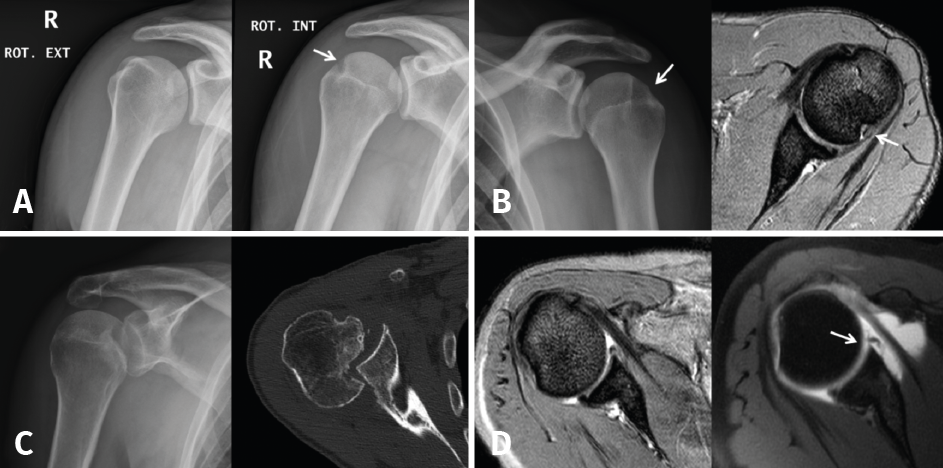

Once the Bankart lesion has been confirmed, we detach and mobilize the capsulolabral complex from the glenoid neck with arthroscopic rasps and/or dissectors until satisfactory and subscapular fibers are visualized (Figure 7). Before implant placement, it is necessary to perform decortication of the anterior glenoid neck using a 4-mm synoviotome. Repair is started after this step, always working from lower to upper.

Figure 7. Detachment and mobilization of the labrum.